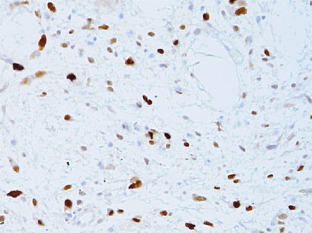

Fig. 1

Fig. 2

Fig. 3

Fig. 4

Fig. 5

Fig. 6

Fig. 7

Fig. 8

Fig. 9

Fig. 10

Fig. 11

Fig. 12

Fig. 13

Fig. 14

Fig. 15

Fig. 16

Fig. 17